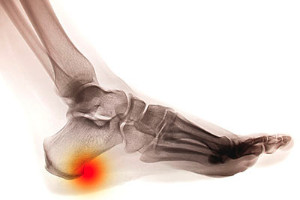

Do I Have a Heel Spur?

The medical condition that is known as a heel spur typically develops from inflammation that happens to the plantar fascia. It is defined as a bony growth that forms on the heel, and can cause pain and discomfort. Some of the reasons why this condition may develop can include sudden weight gain, wearing shoes that do not have adequate cushioning, or existing conditions that may include flat feet. The symptoms that patients experience can consist of pain in the heel and surrounding areas, and the foot may feel stiff upon arising in the morning. Research has indicated that mild relief may be found when orthotics are worn in the shoes, as this may be helpful in reducing pressure on the heel. If you have developed a heel spur, it is suggested that you consult with a podiatrist who can offer you correct treatment options.

Heel spurs are formed by calcium deposits on the back of the foot where the heel is. This can also be caused by small fragments of bone breaking off one section of the foot, attaching onto the back of the foot. Heel spurs can also be bone growth on the back of the foot and may grow in the direction of the arch of the foot.

Older individuals usually suffer from heel spurs and pain sometimes intensifies with age. One of the main condition's spurs are related to is plantar fasciitis.

The pain associated with spurs is often because of weight placed on the feet. When someone is walking, their entire weight is concentrated on the feet. Bone spurs then have the tendency to affect other bones and tissues around the foot. As the pain continues, the feet will become tender and sensitive over time.